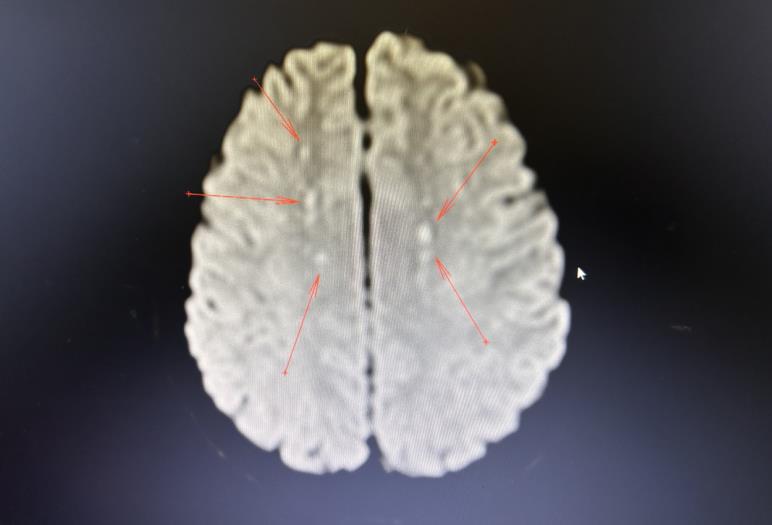

该患者住院第二天突然出现意识下降(GCS10分),失语,躁动不安,呼唤稍有轻微反应,伴随呼吸急促,心率快,口唇轻度紫绀,指脉氧下降,查肺动脉CTA提示肺栓塞,情况紧急,医院重症医学科(ICU)医生立刻参与会诊,并立即将病人转入ICU进行救治。ICU立即加强氧疗,抗凝溶栓处理,病人指脉氧迅速改善,面色红润,但病人意识障碍加重(GCS9分)。ICU钟瑜主任医师详细查看病人,充分了解病史,结合症状、体征及检查检验结果后得出诊断:病人此种情况属于脂肪栓塞综合征,指示予溶栓、抗凝、激素等处理,并完善颅脑MRI检查,证实为急性脑梗死。

患者经ICU积极治疗后,在住院第4天完全清醒,言语流利,对答切题,肢体活动良好。由于病情危重,暂时无法行手术治疗,入院后行骨牵引固定,减轻骨折处疼痛。于住院第6天顺利转出普通病房。住院第11天,复查颅脑CT提示梗死病灶完全消失。病情稳定后于住院第17天行手术治疗,住院第31天顺利出院。